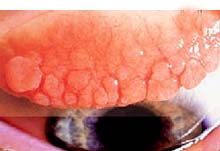

La forma stagionale, acuta, rappresenta circa il 90% di tutte le allergie oculari. Ha un andamento stagionale ed è causata prevalentemente dall'esposizione ai pollini ed alle graminacee (Figura 1). La forma perenne, cronica, persiste durante il corso di tutto l'anno. Questa variante è scatenata per lo più dal contatto con allergeni presenti costantemente nell'ambiente domestico come pelo di animali o polveri di varia origine (sensibilità agli Acari maggiori). Il sintomo predominante della congiuntivite allergica stagionale è un moderato prurito oculare e perioculare (Foto 1), possono essere presenti anche rossore, bruciore, lacrimazione eccessiva, una notevole secrezione di muco filamentoso e rinite. Tuttavia , la congiuntivite allergica acuta può essere scatenata da antigeni che non sono veicolati nell'atmosfera, come ad esempio farmaci, soluzioni per lenti a contatto e conservanti (in questi casi è possibile un meccanimo T-mediato ovvero una sensibilità di tipo ritardato).  La cheratocongiuntivite primaverile è una rara e potenzialmente grave patologia. E' più frequente nell'infanzia, soprattutto nel sesso maschile e di solito si risolve in un periodo variabile tra 4 ed i 10 anni. I pazienti affetti hanno spesso un'anamnesi familiare  di febbre da fieno, allergia, atopia, asma; lamentano intenso prurito, bruciore, lacrimazione, fotofobia. La cheratocongiuntivite atopica è una condizione cronica con esacerbazioni nei mesi invernali che coinvolge tipicamente i giovani intorno ai venti anni di età, con manifestazioni quali febbre da fieno, allergia, eczema, atopia, asma (Figura 2). I pazienti lamentano un prurito costante, bruciore, fotofobia e secrezione acquosa (Foto 2). La congiuntivite gigantopapillare (Foto 3) è più frequente in pazienti portatori di lenti a contatto (soprattutto morbide), ma si può riscontrare anche in soggetti con protesi oculari e suture corneali post-chirurgiche. Può essere causata da una reazione di ipersensibilità della congiuntiva ai depositi presenti sulla superficie della lenti, oppure dallo sfregamento continuo della congiuntiva sul bordo della lente stessa. I sintomi sono caratterizzati da discomfort del bordo palpebrale o dolore derivante dalla rimozione delle lenti stesse, annebbiamento visivo e lieve secrezione mucosa. Con il passare del tempo, si ha la sensazione di corpo estraneo, bruciore, lacrimazione, aumentata secrezione ed intolleranza alle lenti a contatto. La storia clinica, l’esame obbiettivo i test in vivo (prick e talvolta patch-test) (Figure 3 e 4) e la ricerca delle IgE totali e specifiche (RAST) permette una agevole diagnosi. Talvolta è utile uno striscio congiuntivele che evidenzia ricchezza di eosinofili nel secreto. Nelle forme gigantofollicolari vi è grande abbondanza di linfociti. La diagnosi clinica non è sempre agevole. La congiuntivite allergica si manifesta in genere con arrossamento degli occhi, prurito, lacrimazione e intolleranza alla luce. I sintomi anzidetti insorgono improvvisamente a seguito dell’esposizione agli allergeni. Nella congiuntivite di tipo allergico, a differenza di quanto può avvenire nelle forme virali e batteriche, i sintomi a carico dell’occhio non sono quasi mai isolati ma si accompagnano ad analoghe manifestazioni a carico delle mucose nasali (oculorinite). Nelle forme solo congiuntivele la D.D. rispetto a forme batteriche o virali senza l’ausilio dei test allergologici e del laboratorio è pressoché impossibile. La terapia più efficace consiste nell’evitare per quanto possibile di entrare in contatto con gli allergeni. Questo è ragionevolmente semplice per chi è allergico al pelo degli animali domestici, molto più complicato per chi è allergico al polline o agli acari della polvere che sono in pratica dappertutto. Nei casi più lievi si ricorre a colliri con associazioni di antistaminici (levocabastina) e vasocostrittori (pseudoefedrina), ovvero contenenti antinfiammatori non steroidei (diclofenac). Nei casai più severe si usano, 2-3 volte al dì, colliri con stabilizzanti di membrana (cromoglicato disodico o nedocromile). Gli steroidi usati per lungo tempo sono proinfettivi e aumentano il tono oculare. I vasocostrittori, invece, possono indurre effetti rimbalzo. Gli antistaminici per via sistemica sono poco utili in caso di interessamento esclusivamente oculare e vanno riservati alle forme oculo-nasali (raffreddore da fieno).

Foto 3